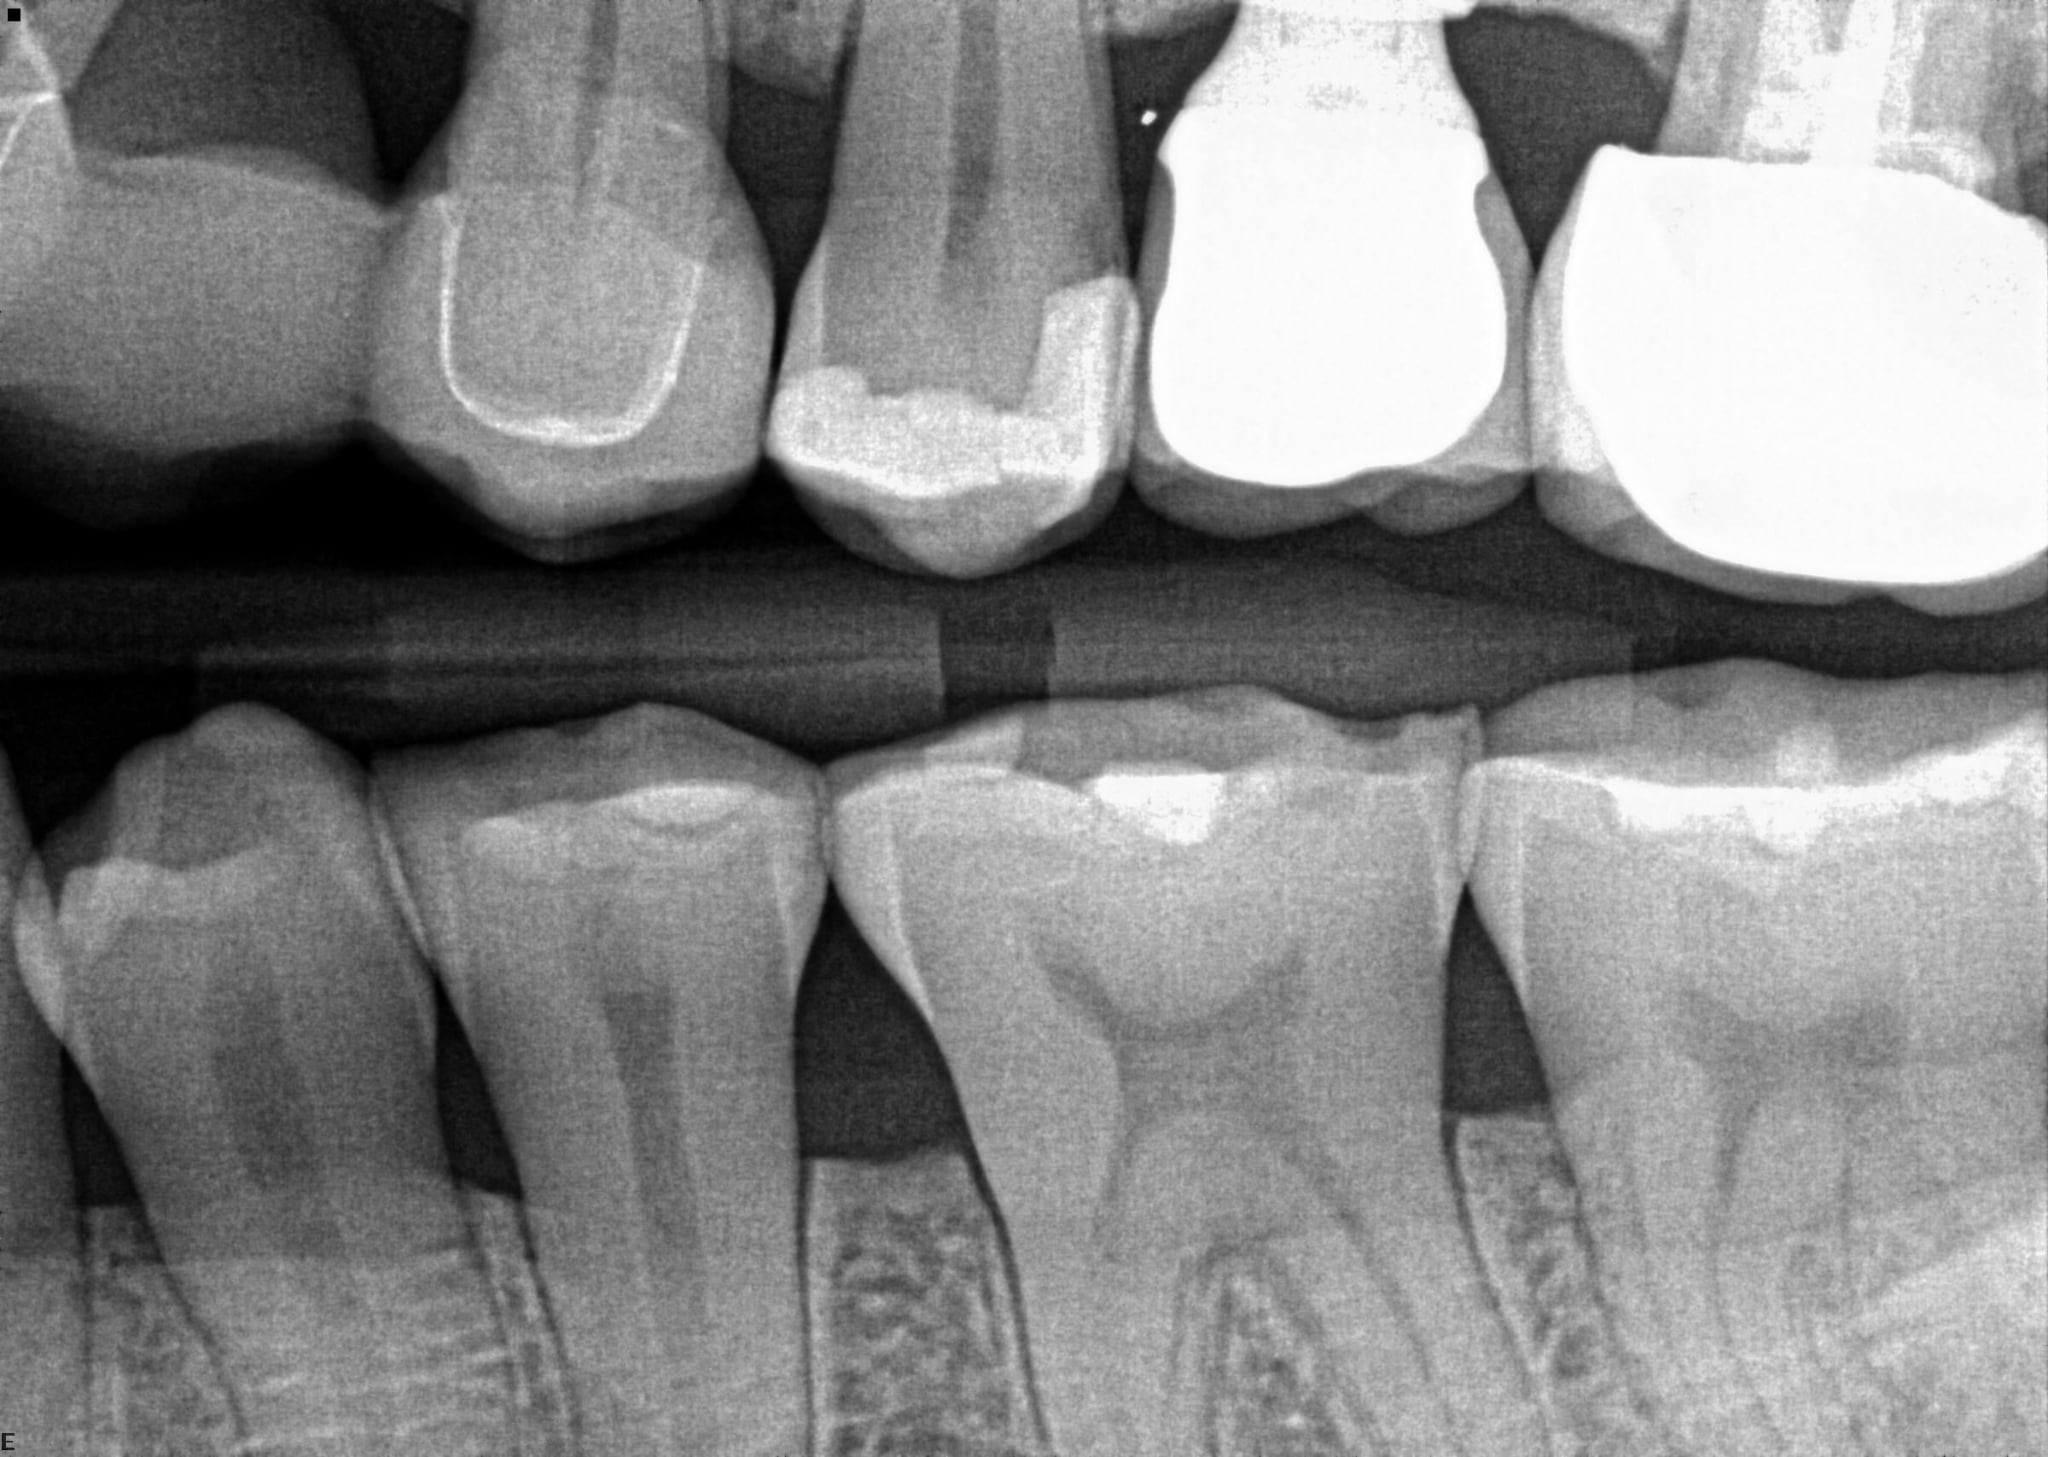

1. On which surface a recurrent caries can be detected?

2 / 35

2. On which surface a recurrent caries can be detected?

None of the teeth shows recurrent caries